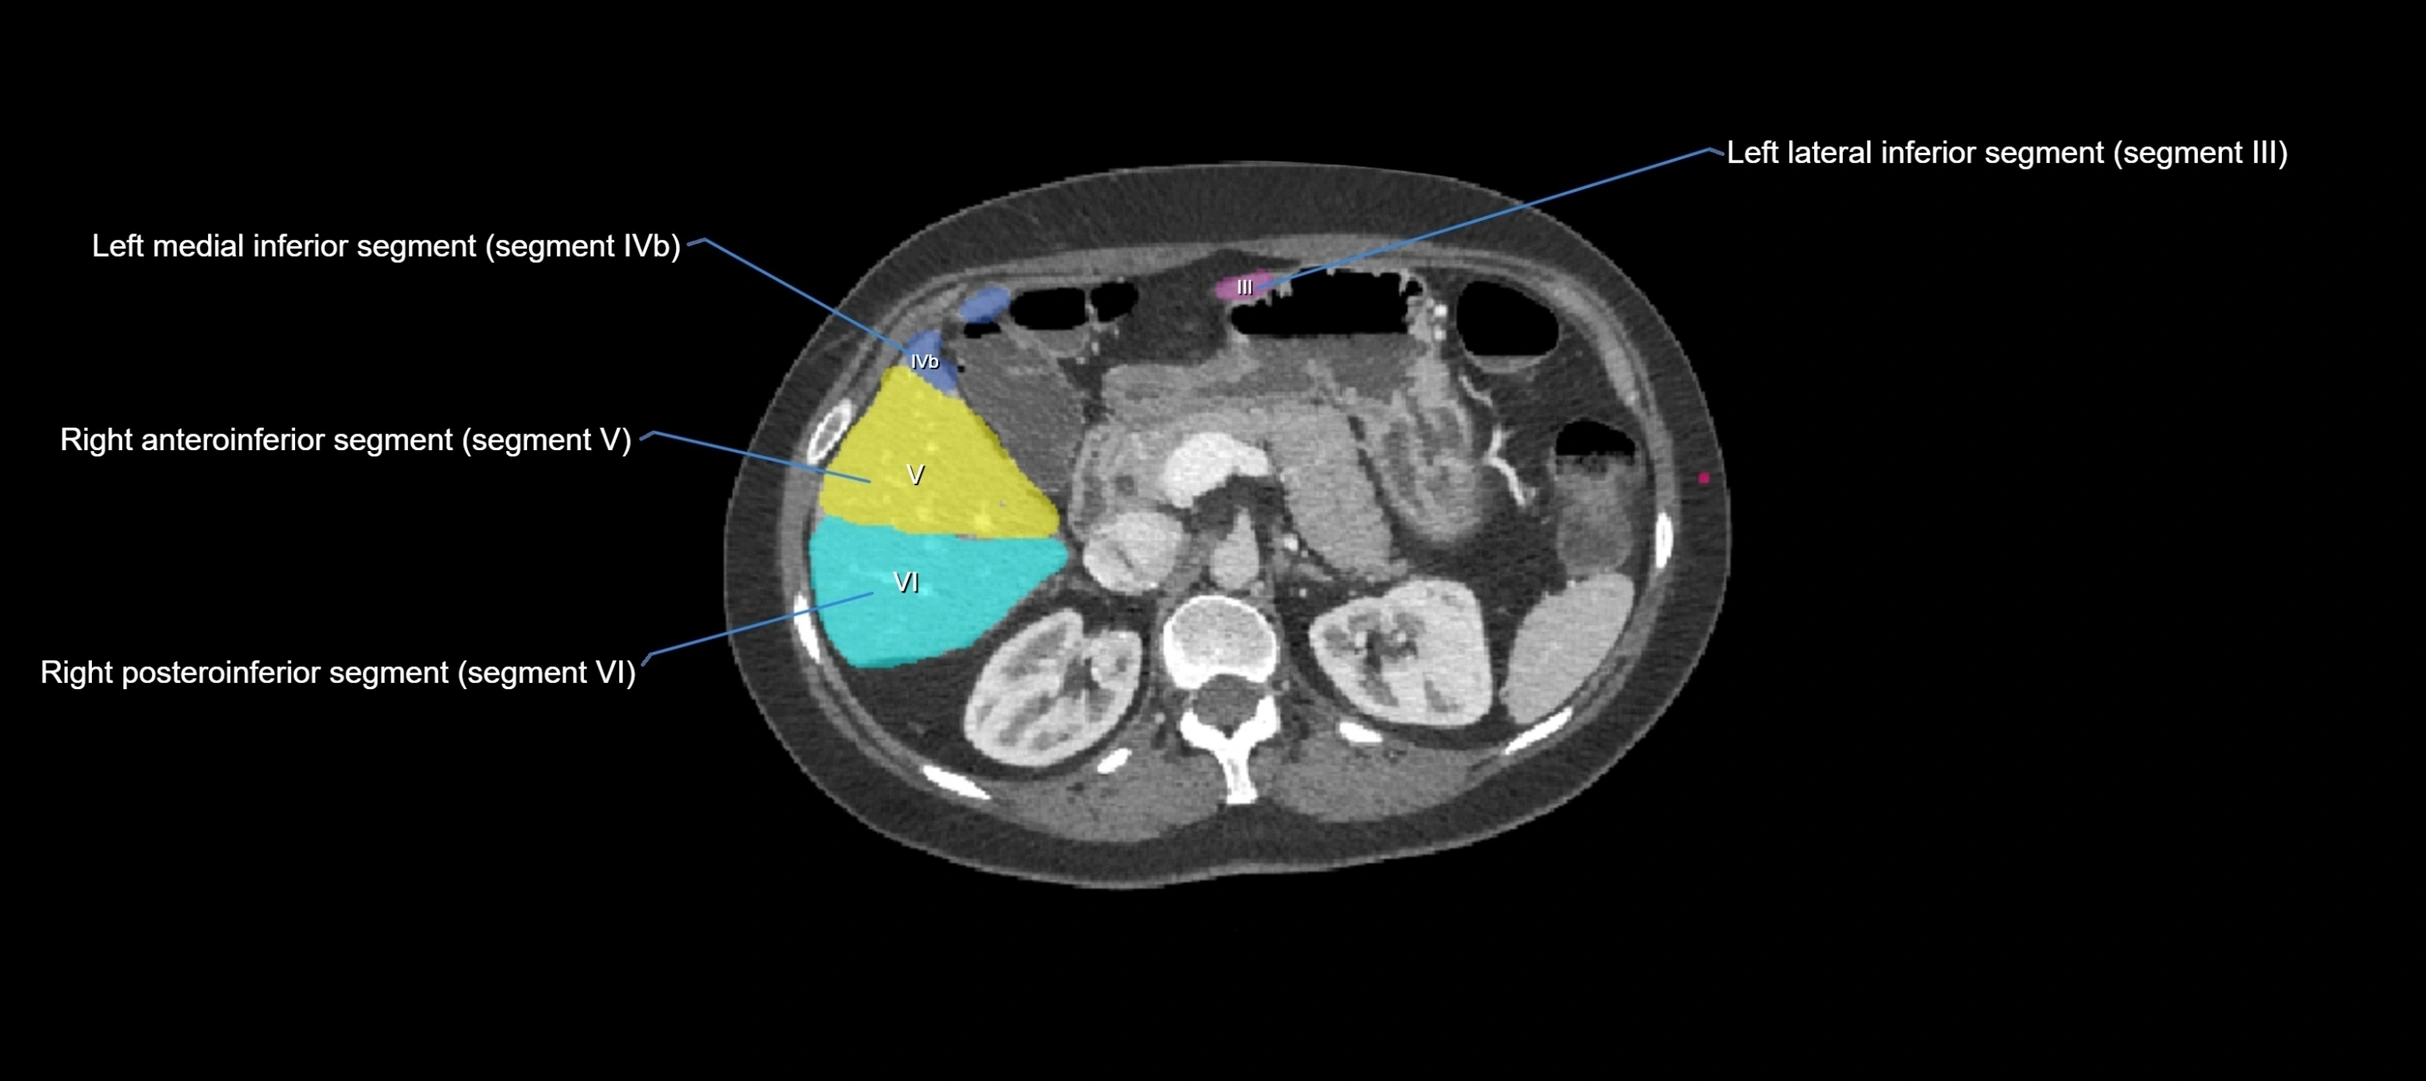

CT Appearance

CT Pre-Contrast:

• Caudate lobe appears as a soft-tissue density, isodense to the rest of the liver

• Enlargement may be appreciated in cirrhosis or Budd–Chiari syndrome

CT Post-Contrast:

• Homogeneous enhancement in the portal venous phase, similar to rest of liver

• Independent venous drainage into the IVC may be visualized

• Lesions follow characteristic CT enhancement patterns (HCC: arterial hyperenhancement with washout; hemangiomas: peripheral nodular enhancement with centripetal fill-in)

CT Venous Phase (functional significance):

• Caudate lobe often enhances relatively more than other lobes in Budd–Chiari syndrome, due to preserved venous outflow

CT Image

image